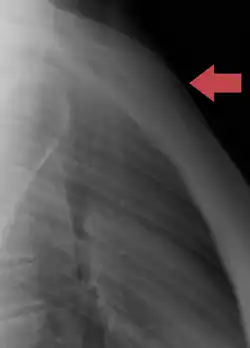

Position of the sternum (red)